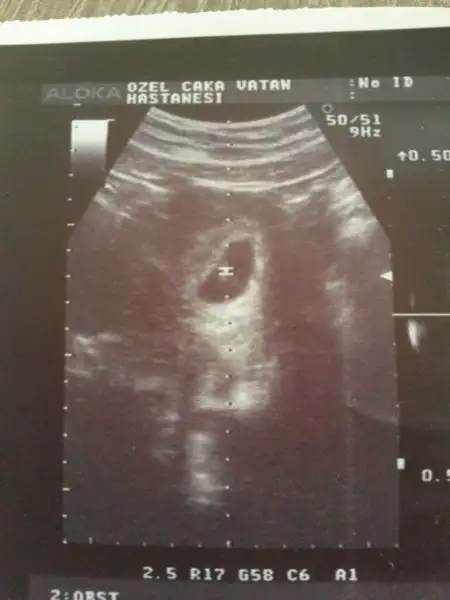

rus cinsiyet takvimini denemedim canım. çünkü eşim neredeyse her yıl kan bağışında bulunur. kan bağışı yapan çiftlerde bu takvim tutmuyormuş. benim de daha 10 hafta dolmadı. ultrason fotoları atayım ama daha çok küçük pek bir şey anlaşılacağını düşünmüyorum ama yine de bakarsanız sevinirimBende çin takvimi, rus cinsiyet takvimi ,biyoloji takvimde denedim kiz diyor.. arti meyve hic sevmem tatli sevmem tuzlu eksi hic birinide sevmem.. netteki butun belirtilere gore alyans yuzuge kadar hepsinde kiz cikiyor...usg resmindede sagda yani ordada kiz.. ki bende tecrubeli bir anne olarak kiz diyorim. 2 hafta sonra gidecem dr. Bakalim o ne diyecek :))))

Eki Görüntüle 1707425 Eki Görüntüle 1707427 birde benim miniğime bakarmısınız hanımlar bu 7+4 günlük ultrason görüntüsü

vayyy terbiyesiz, öyle oyunlar yapmayı da öğrenmiş yani şimdiden, çok işim var benim diyosunuz :)Cnm senin bebek bizimle oynuyor:)ilk resimde solda ikinci resimde sağda o yüZden yorum yapmayacağım.sen 11 12 haftalık fotosunu atarsin ilerde o zaman nubuna bakarım.

Benim tahminim eğer karından bakıldıysa bu bebek kızEki Görüntüle 1707425 Eki Görüntüle 1707427 birde benim miniğime bakarmısınız hanımlar bu 7+4 günlük ultrason görüntüsü

sanki sola daha yakın gibi değilmi ? yani ben oğlum olsun çok istiyorum da :)Benim tahminim eğer karından bakıldıysa bu bebek kız

canım bana da sağa daha yakın gıbı geldi:) rabbim gönlündekini hakkında hayırlı eğlesin inşsanki sola daha yakın gibi değilmi ? yani ben oğlum olsun çok istiyorum da :)